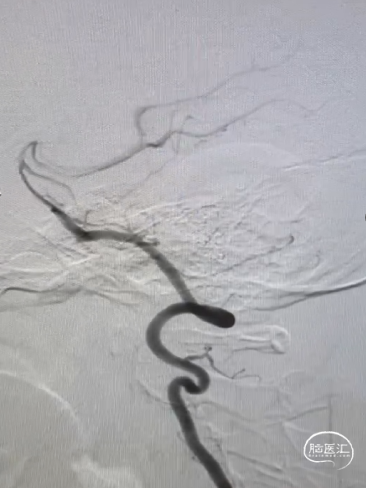

术前造影

CTA提示:右侧大脑中动脉动脉瘤。

造影提示:动脉瘤瘤颈累及上下干支,下干支与M1成角较锐S弯;患者右侧颈内动脉非常迂曲。

3D造影成像:动脉瘤大小约3.7*3.1mm。

其它颅内血管未见异常。